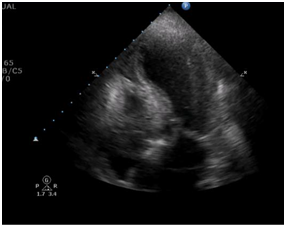

Transthoracic echocardiogram at admittance

After admittance, the patient underwent a transthoracic echocardiogram where we observed a left ventricle outflow tract gradient of 91 mmHg, as well as apical dyskinesia (Figure 2 & 3).

Figure 2 Left ventricle outflow gradient of 91 mmHg (Taken at admittance).

Figure 3 Left ventricle apical dyskinesia as seen with a 4 chamber apical view.